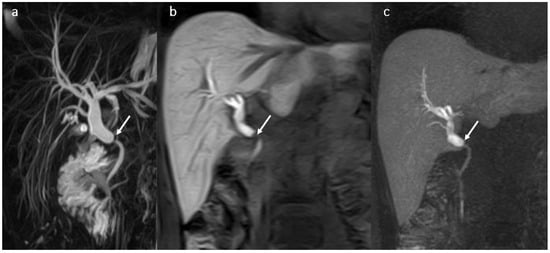

3.7. BT Lithiasis